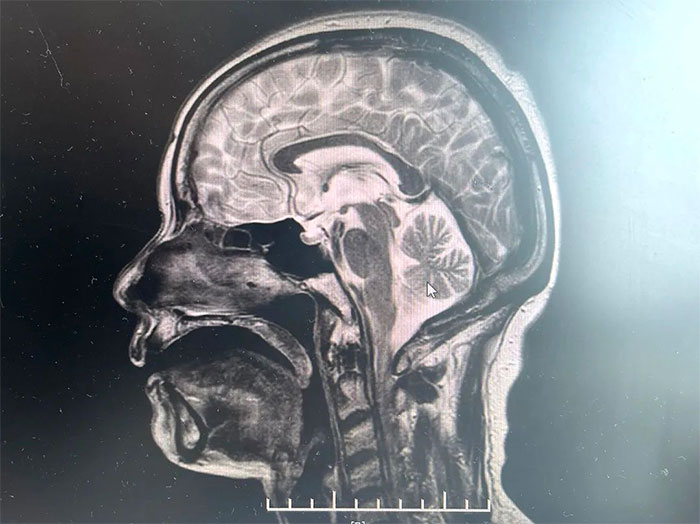

▲ MRI影像提示符合多系统萎缩表现

经磁共振(MRI)检查显示,林女士桥脑“十字征”、“壳核裂隙征”、“小脑萎缩”,符合多系统萎缩影像表现,再次验证了李振并主任的临床判断——多系统萎缩。